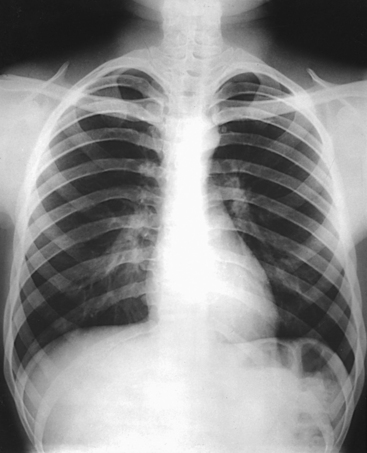

Structures shown: PA projection of the thoracic viscera shows the air-filled trachea, the lungs, the diaphragmatic domes, the heart and aortic knob, and, if enlarged laterally, the thyroid or thymus gland (Fig. 10-32). The vascular markings are much more prominent on the projection made at the end of expiration. The bronchial tree is shown from an oblique angle. The esophagus is well shown when it is filled with a barium sulfate suspension.